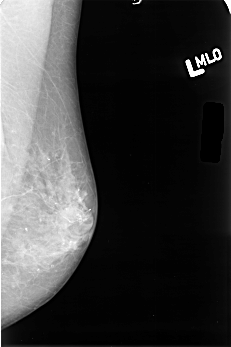

B_3380_1.LEFT_MLO

B_3380_1.LEFT_CC

LEFT_MLO LINES 4504 PIXELS_PER_LINE 2992 BITS_PER_PIXEL 12 RESOLUTION 50 NON_OVERLAY